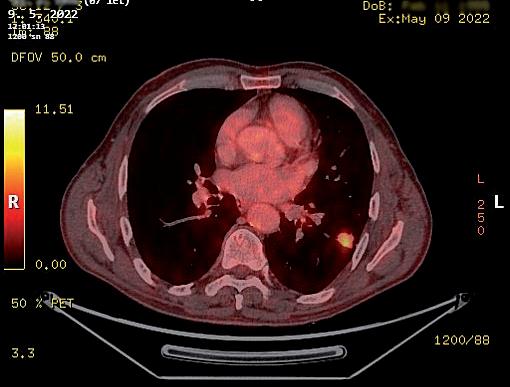

obr. 3.6 Parahilózněně a blízko tepenných struktur hilu lokalizované 2cm metabolicky aktivní ložisko v horním laloku vlevo na CT (a) a PET CT (b) obraze, které se opakovaně paraklinickými metodami nezdařilo mikromorfologicky určit. Bezpečná peroperační biopsie takto umístěného ložiska jeho kompletním vynětím neanatomickou (klínovitou) resekcí je problematická či spíše nemožná videotorakoskopicky i otevřeně

Pro posouzení indikace k operaci je ideálním stavem ná dor již histologicky verifikovaný jako maligní nemalobu něčný tumor plic a aktuální PET CT vyšetření zobrazující úroveň metabolické aktivity ve spádových lymfatických

uzlinách. Indikující chirurg je však často v situaci, kdy se primární ložisko v plíci podezřelé z maligního původu nezdařilo verifikovat bronchoskopií s biopsií nebo kar táčkovou cytologií, ani punkční transparietální biopsií pod CT (obr. 3.9, 3.10).

Na tomto místě je potřeba z praxe uvést, že výraz nou pomocí pro předoperační posouzení, jestli je nádor plíce zhoubný nebo nezhoubný, nemusí být ani PET CT [35, 36], které je v dnešní době jinak zásadním vyšet řením (obr. 3.11). Nevelké metabolicky aktivní ložisko i s aktivitou spádových uzlin může být počínající plicní malignitou, ale také zánětlivým procesem (obr. 3.12). Objemnější, asymptomatický, náhodně objevený, cent rálně v laloku umístěný nádor s výraznou metabolickou aktivitou, včetně nepravidelné metabolické aktivity uz lin u uhlokopa, může být jen koniotickým uzlem (obr. 3.13). Naopak jako neaktivní nemusí být zobrazeny pouze zhoubné nádory pod aktuálním kritickým roz lišovacím objemem pro PET CT (průměr léze 8 mm).